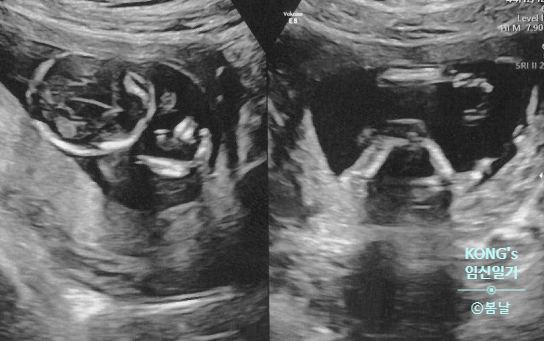

[임신 10~12주차] 임신 초기 극복! 일상 기록 / 갑상선 항진증 재검 / 쇼파구매 / 1차 기형아 검사 (목덜미 투명대 검사)

임신 15주차에 몰아 쓰는 임신 초기 일기들 ㅋㅋ 더이상 뒷북일 수 없다...!! * 10주 ~ 12주 : 2024/01/16 ...